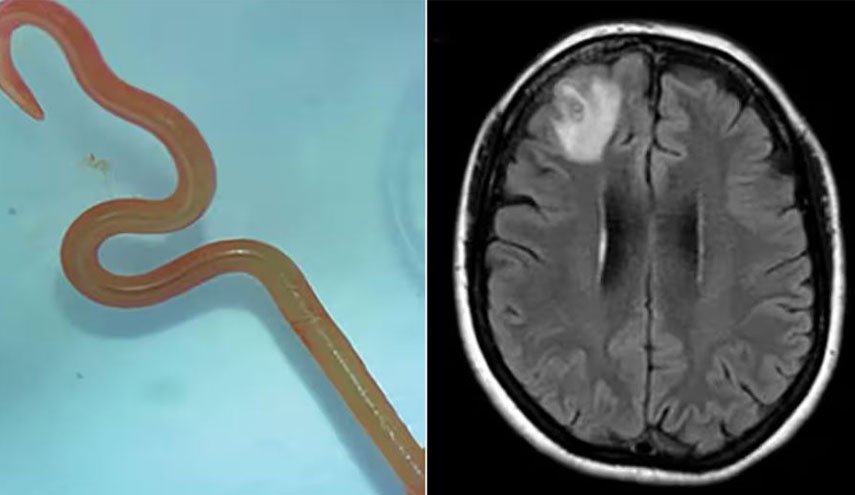

وأضافت: "الأكثر شيوعًا دودة شريط لحم الخنزير، تينيا سوليوم (أو داء الكيسات العصبية)".

والطريقة الأساسية لانتقال هذه الديدان لأدمغتنا هي عن طريق الخنزير لا سيما عندما يستهلك لحم الخنزير النيء أو غير المطبوخ جيدا ما يسمح لهذه الدودة الشريطية بالدخول لأجسامنا.

بحسب بيتسي فإن هذه الدودة لا يمكنها الانتقال إلى الدماغ لكن يرقاتها يمكنها ذلك، حيث تضع الدودة يرقاتها بمجرد دخولها للأمعاء مستخدمة أجسامنا كوسيط، وإذا لم يتم طرد البيض من أجسامنا من خلال البراز، فقد تنمو إلى يرقات.

يمكن لهذه اليرقات أن تنتقل إلى أعضاء أخرى من خلال مجرى الدم، قد تنتقل هذه الديدان الشريطية أيضا من إنسان إلى آخر إذا كان لدى الشخص عادات غير صحية مثل عدم غسل يديه جيدًا بعد استراحة الحمام.